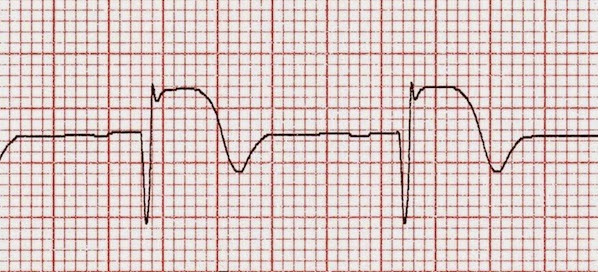

BMJ, 7 de noviembre de 2018 Aunque la incidencia de infarto de miocardio (IM) fue mayor en los hombres que en las mujeres, varios factores de riesgo se asociaron más intensamente con el IM en las mujeres en comparación con los hombres. Las asociaciones específicas por sexo entre los factores de riesgo y el IM disminuyeron con la edad, pero, donde ocurrió, se mantuvo el mayor riesgo relativo en las mujeres. A medida que la población envejece y la prevalencia de factores de riesgo asociados con el estilo de vida aumenta, la incidencia de IM en las mujeres probablemente se volverá más parecido a la de los hombres.